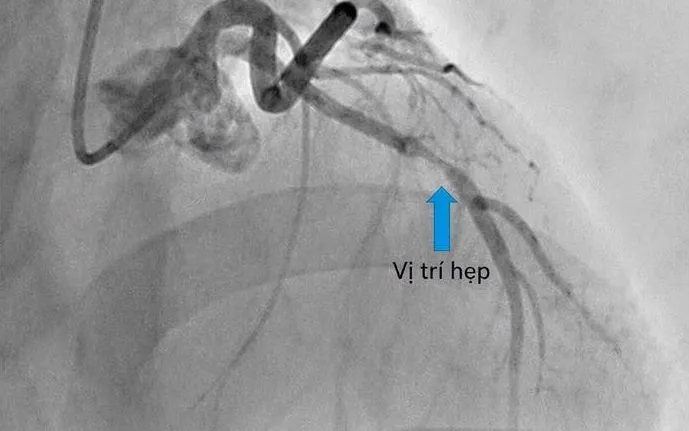

Ekip can thiệp tim mạch của Bệnh viện Đa khoa số 2 tỉnh Lào Cai đã tiếp nhận và tiến hành chụp mạch vành cấp cứu. Kết quả cho thấy stent cũ tại động mạch liên thất trước vẫn còn thông, nhưng xuất hiện tình trạng tái hẹp trong stent khoảng 80%, làm giảm đáng kể dòng máu nuôi cơ tim.

Các bác sĩ chẩn đoán bệnh nhân bị tái hẹp trong stent - một biến chứng nguy hiểm có thể dẫn đến nhồi máu cơ tim cấp nếu không được xử trí kịp thời.

Ngay sau đó, ekip đã tiến hành nong mạch và đặt thêm một stent phủ thuốc để tái lập dòng chảy mạch vành. Sau can thiệp, tình trạng người bệnh ổn định, các triệu chứng cải thiện rõ rệt và thoát khỏi nguy cơ nhồi máu cơ tim.